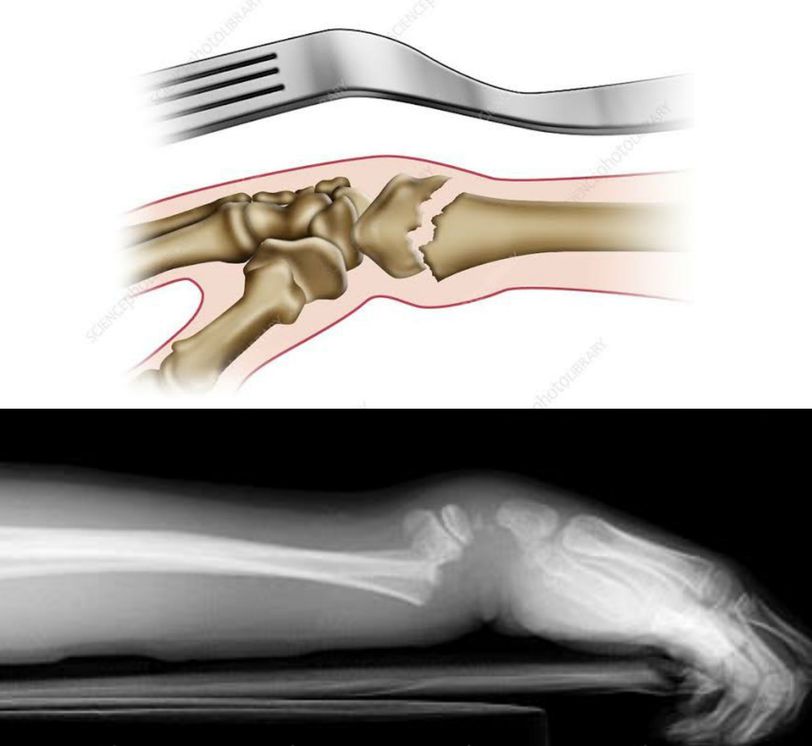

Colles fracture or dinner fork deformity is a complete transverse fracture of the distal 2cm of the radius. The fractured bone is displaced posteriorly which results in shortening of the radius. This produces a dinner fork appearance due to posterior angulation in the forearm just proximal to the wrist. This fracture results from forced extension of the hand e.g. in slipping or in an attemp to break a fall and landing on forearm and hand in extended and pronated position. Osteoporotic women are particularly vulnerable. Image via: https://images.app.goo.gl/ePwdDLSq4xDmqWDe7 https://images.app.goo.gl/TKTNTf6NMaWSqWVRA